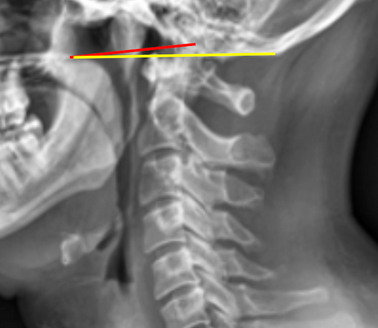

Image Type Cervical Spine X-Ray CT Scan MRI Scan Atlantodental Interval (ADI) Basion-Axial Interval Basion-Dens Interval (BDI) C2 Tilt C2–C7 Coronal Cobb Angle Cervical C2-7 lordosis C2-C7 Translation Chamberlain’s Line / McGregor’s Line Flexion-Extension George’s Line (Posterior Cervical Line) K-Line Interpedicular Distance (IPD) Occiput-C2 Angle Occipital Condyle–C1 Interval (CCI) Posterior Atlantodental Interval (PADI) Power’s ratio Sagittal Canal Diameter Sagittal Vertical Axis (SVA) Spinolaminar line Swischuk Line T1 Slope Torg/Pavlov Canal-to-Body Ratio